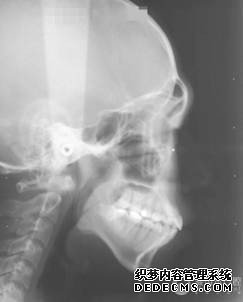

临床诊断:通过3D数字化全景机的拍片检查,患者上下牙排列拥挤,前牙受挤压向内歪斜,咬合关系异常,唇形尚可,颞下颌关节检查未见异常,无蛀牙、牙周疾病症状。经过和患者商量,选定自锁托槽矫正方案,调整牙间隙,恢复牙齿的正常排列,实现正常的咬合关系。

全景机侧位片